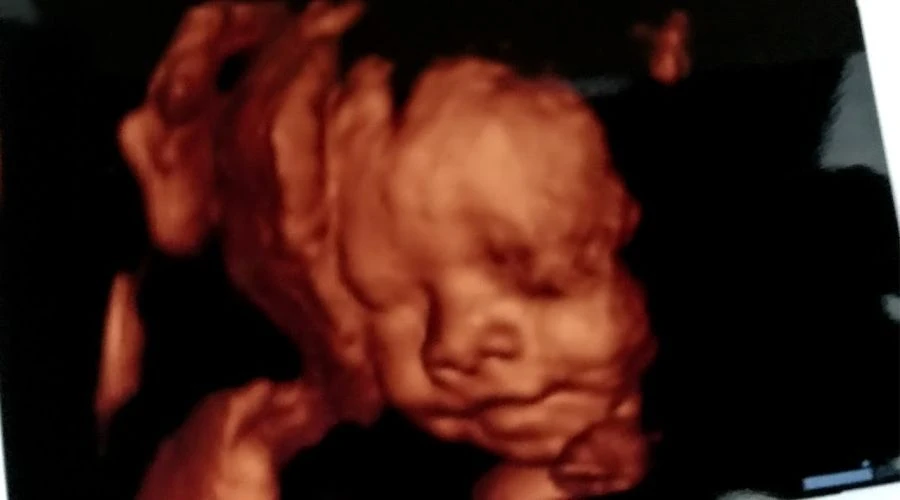

"Con matar o abortar no se van a arreglar los problemas sociales", subrayó, y señaló que "queremos salvar dos vidas: la vida de la mujer y la vida de las personas en el vientre".